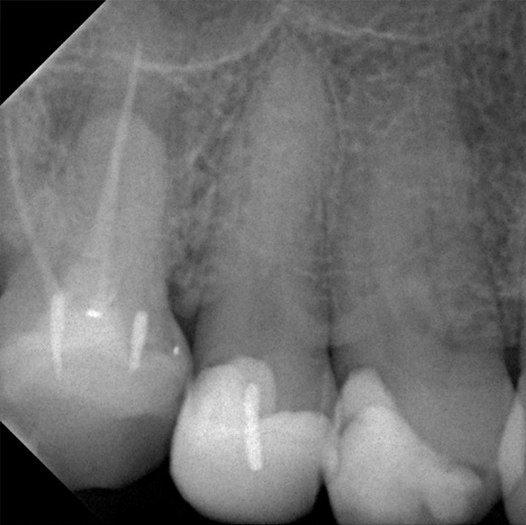

Before

Before Root Canal treatment